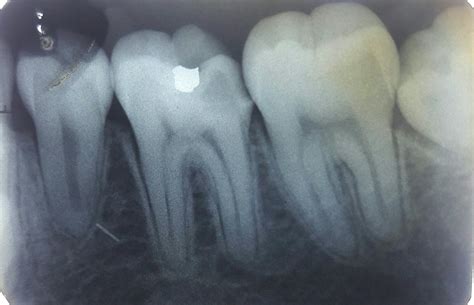

Not all X-rays are the same, and your dentist will choose the specific type based on your symptoms and oral history. The most common tool for spotting decay is the bitewing X-ray. During this process, you bite down on a specialized piece of film or a sensor, which captures a clear view of the crowns of both your upper and lower teeth on one side of your mouth.

Bitewing Detecting cavities between teeth and checking the height of bone.

When looking at your own X-rays on a monitor, you might find them confusing. Dentists are trained to identify specific visual cues. In a tooth decay X-ray, enamel—the hardest substance in your body—appears as a bright white or light gray area. Healthy bone also shows up in varying shades of white. When tooth decay is present, it appears as a darker, shadowy spot on the image.

This happens because the demineralization caused by bacteria makes the tooth structure less dense, allowing more X-ray radiation to pass through the area. The less dense the tissue, the darker it appears on the radiograph. If your dentist points out a dark spot on your X-ray, they are identifying an area where the mineral content of your tooth has been compromised by acid-producing bacteria.